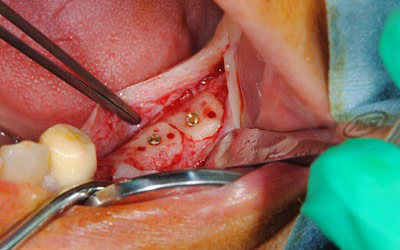

インプラントを埋入するためには、骨を増やさなければならず、患者様ご自身の骨を移植する、自家骨移植術を行なうこととしました。写真、青色の矢印で示す、智歯周辺の骨を採取し、黄色の矢印の部位に骨片を移植、チタン製の小さなスクリューで骨片を固定するという手術を行いました。細く、白く映っているのが骨を固定したミニスクリューです。

写真は、実際の手術の写真で、丸く採取された骨片が、スクリューで固定されています。